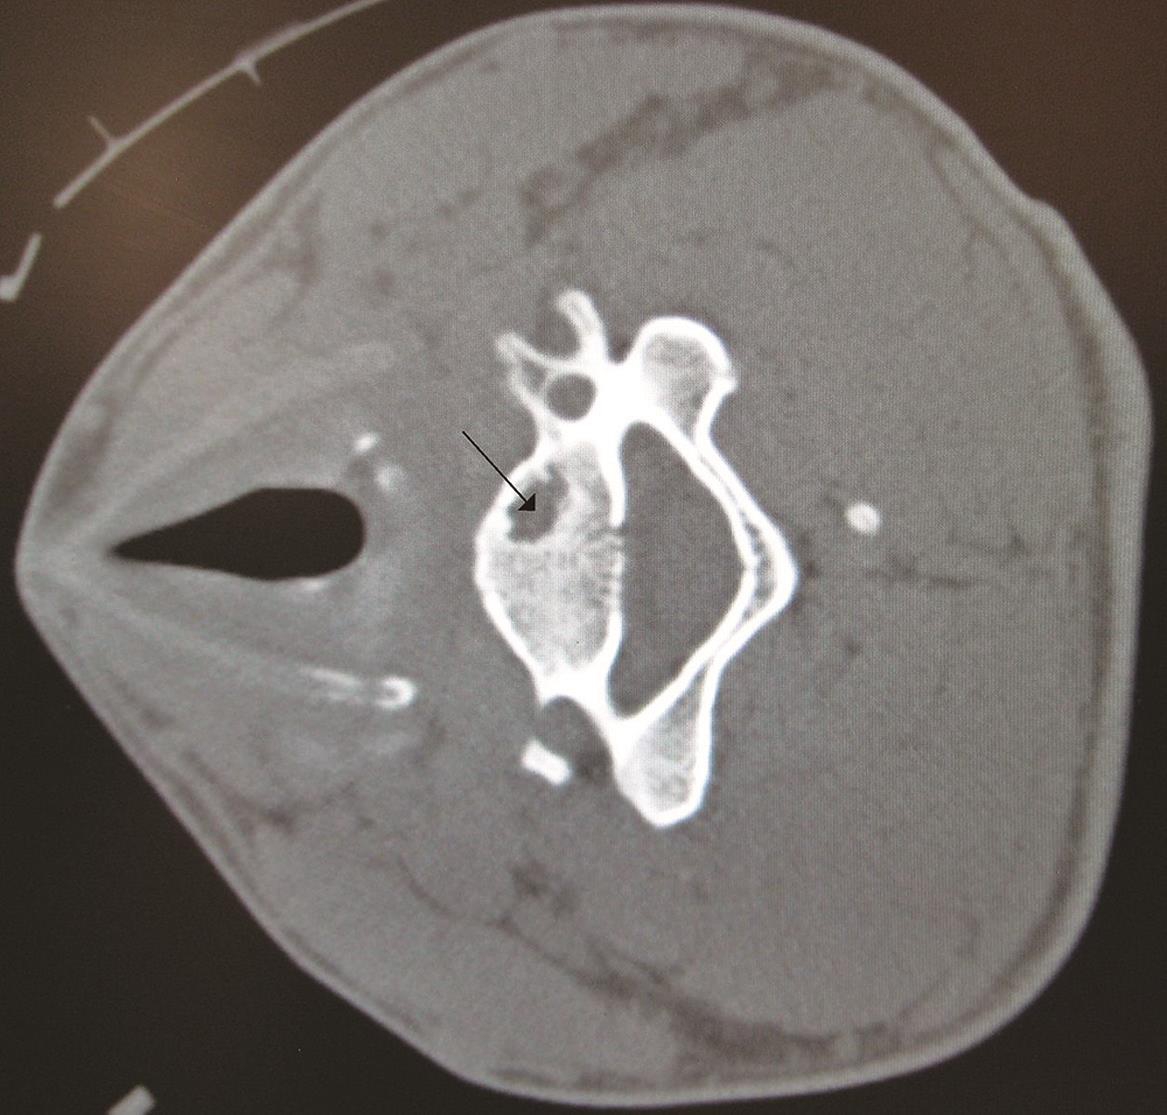

CT影像下所见颈部椎骨的骨囊肿(黑

有些良性骨肿瘤患者没有任何症状,只是在诊断其他疾病中,进行影像学检查中意外发现。